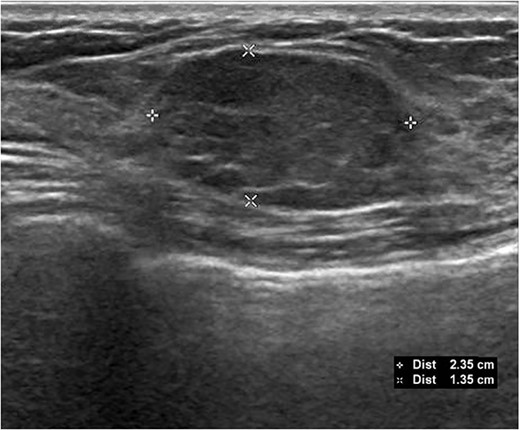

A 26-year-old female presented with a longstanding palpable fibroadenoma in the left breast. She was first investigated with ultrasound imaging showing a lobulated 2.4 × 2.5 × 1.4 cm hypoechoic lesion with well-defined margins (Fig. 1). She underwent core needle biopsy of the lesion which was histologically proven to be a fibroadenoma. There was no evidence of malignancy. She was later discharged and presented 6 years later with a history of recent enlargement of the left breast lump. Ultrasound imaging now showed increase in the size of the left breast fibroadenoma to 3.2 × 2.7 × 1.6 cm and development of an irregular outline (Fig. 2). Because of increasing size of the lesion and new indeterminate features, excision biopsy was advised. Post-excision histology revealed a 5-mm focus of classic lobular carcinoma in situ (LCIS) with a 0.6-mm area of microinvasive carcinoma within the fibroadenoma (Figs 3–6). The carcinoma was estrogen and progesterone receptor positive and Her2 negative. Atypical ductal hyperplasia was seen in the breast tissue adjoining the fibroadenoma. After presentation at our multidisciplinary tumor board, sentinel lymph node biopsy for staging of the invasive carcinoma, radiotherapy and endocrine therapy for risk and recurrence reduction, as well as genetic testing in view of her young age was discussed with the patient. Because of the small size of the invasive carcinoma, potential cost and morbidity associated with sentinel lymph node biopsy, no further surgery was performed. The patient was agreeable to proceed with radiotherapy and endocrine therapy but requested to defer genetic testing.

Subsequent ultrasound demonstrating increase in size of the left breast mass now measuring 3.2 × 2.7 × 1.6 cm. There was also new development of irregular margins, giving an indeterminate appearance.